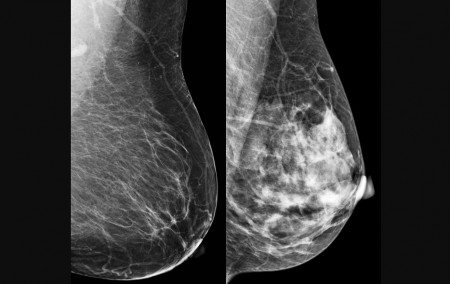

Breast cancer is the leading cause of cancer death in women (image: CDC)

The National Cancer Institute (INCA) notes that breast cancer is one of the most prevalent cancers among Brazilian women (excluding non-melanoma skin cancer) and the leading cause of cancer-related death among women. The estimated figures for total breast cancer diagnoses in 2025 point to 73,000 new cases, with the Southeast being the region with the highest incidence, according to the publication Breast Cancer Control in Brazil: Data and Figures 2025, which was released to mark Pink October, a month dedicated to raising awareness and fighting the disease.